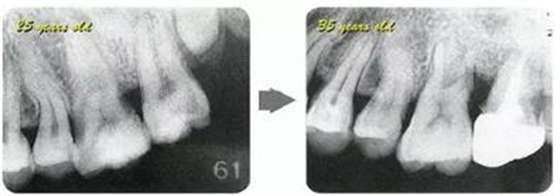

參考病例① 35歲女性

在左下第一磨牙在25歲時(shí)近中處可以看到垂直性的骨吸收,但35歲時(shí)吸收停止,原本沒(méi)有見(jiàn)到的遠(yuǎn)中處骨吸收的,現(xiàn)在卻吸收得很?chē)?yán)重。

在右下處,原本有大量骨吸收的第一磨牙處的吸收卻變緩慢,原本沒(méi)有吸收的第二前磨牙卻出現(xiàn)了吸收。出現(xiàn)吸收的左上第一磨牙的遠(yuǎn)中處,吸收得越來(lái)越多了。

把10年間的變化做成表格。牙周病的發(fā)展根據(jù)各個(gè)人會(huì)不同,即使通一個(gè)人,不同牙齒,不同牙面發(fā)展的狀態(tài)也不同。